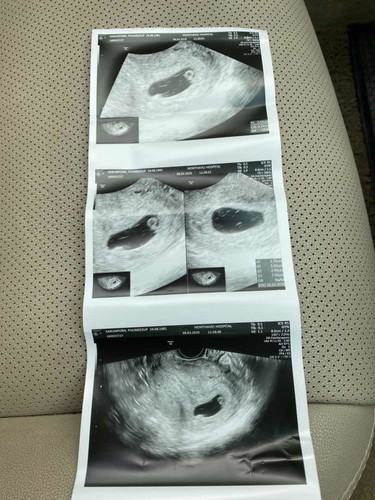

ตรวจทางช่องคลอด 6 week ตัวอ่อน 0.19 cm. เครียดมากเลย กลัวท้องลม?

ถ้าเห็นตัวอ่อน แสดงว่าตั้งครรภ์ปกติจ้า แต่ต้องรอดูว่าน้องมีหัวใจหรือป่าว บ้านนี้ซาว ตอน 6w5d ได้ยินเสียงหัวใจน้องแล้วค่ะ

ท้องลมคือไม่มีตัวอ่อน อันนี้มีแล้ว ไม่ลมแน่นอน รอแค่มีเสียงหัวใจ กับ การเจริญเติบโตของน้องว่าสมบูรณ์มั้ย อย่ากังวล

ไม่น่าจะท้องลมค่ะ เพราะตอนท้องน้องตอน6วีคก็เพิ่งเจอถุงการตั้งครรภ์ และก็ต้องมาฟังเสียงหัวใจน้องด้วยค่ะว่าเต้นไหม